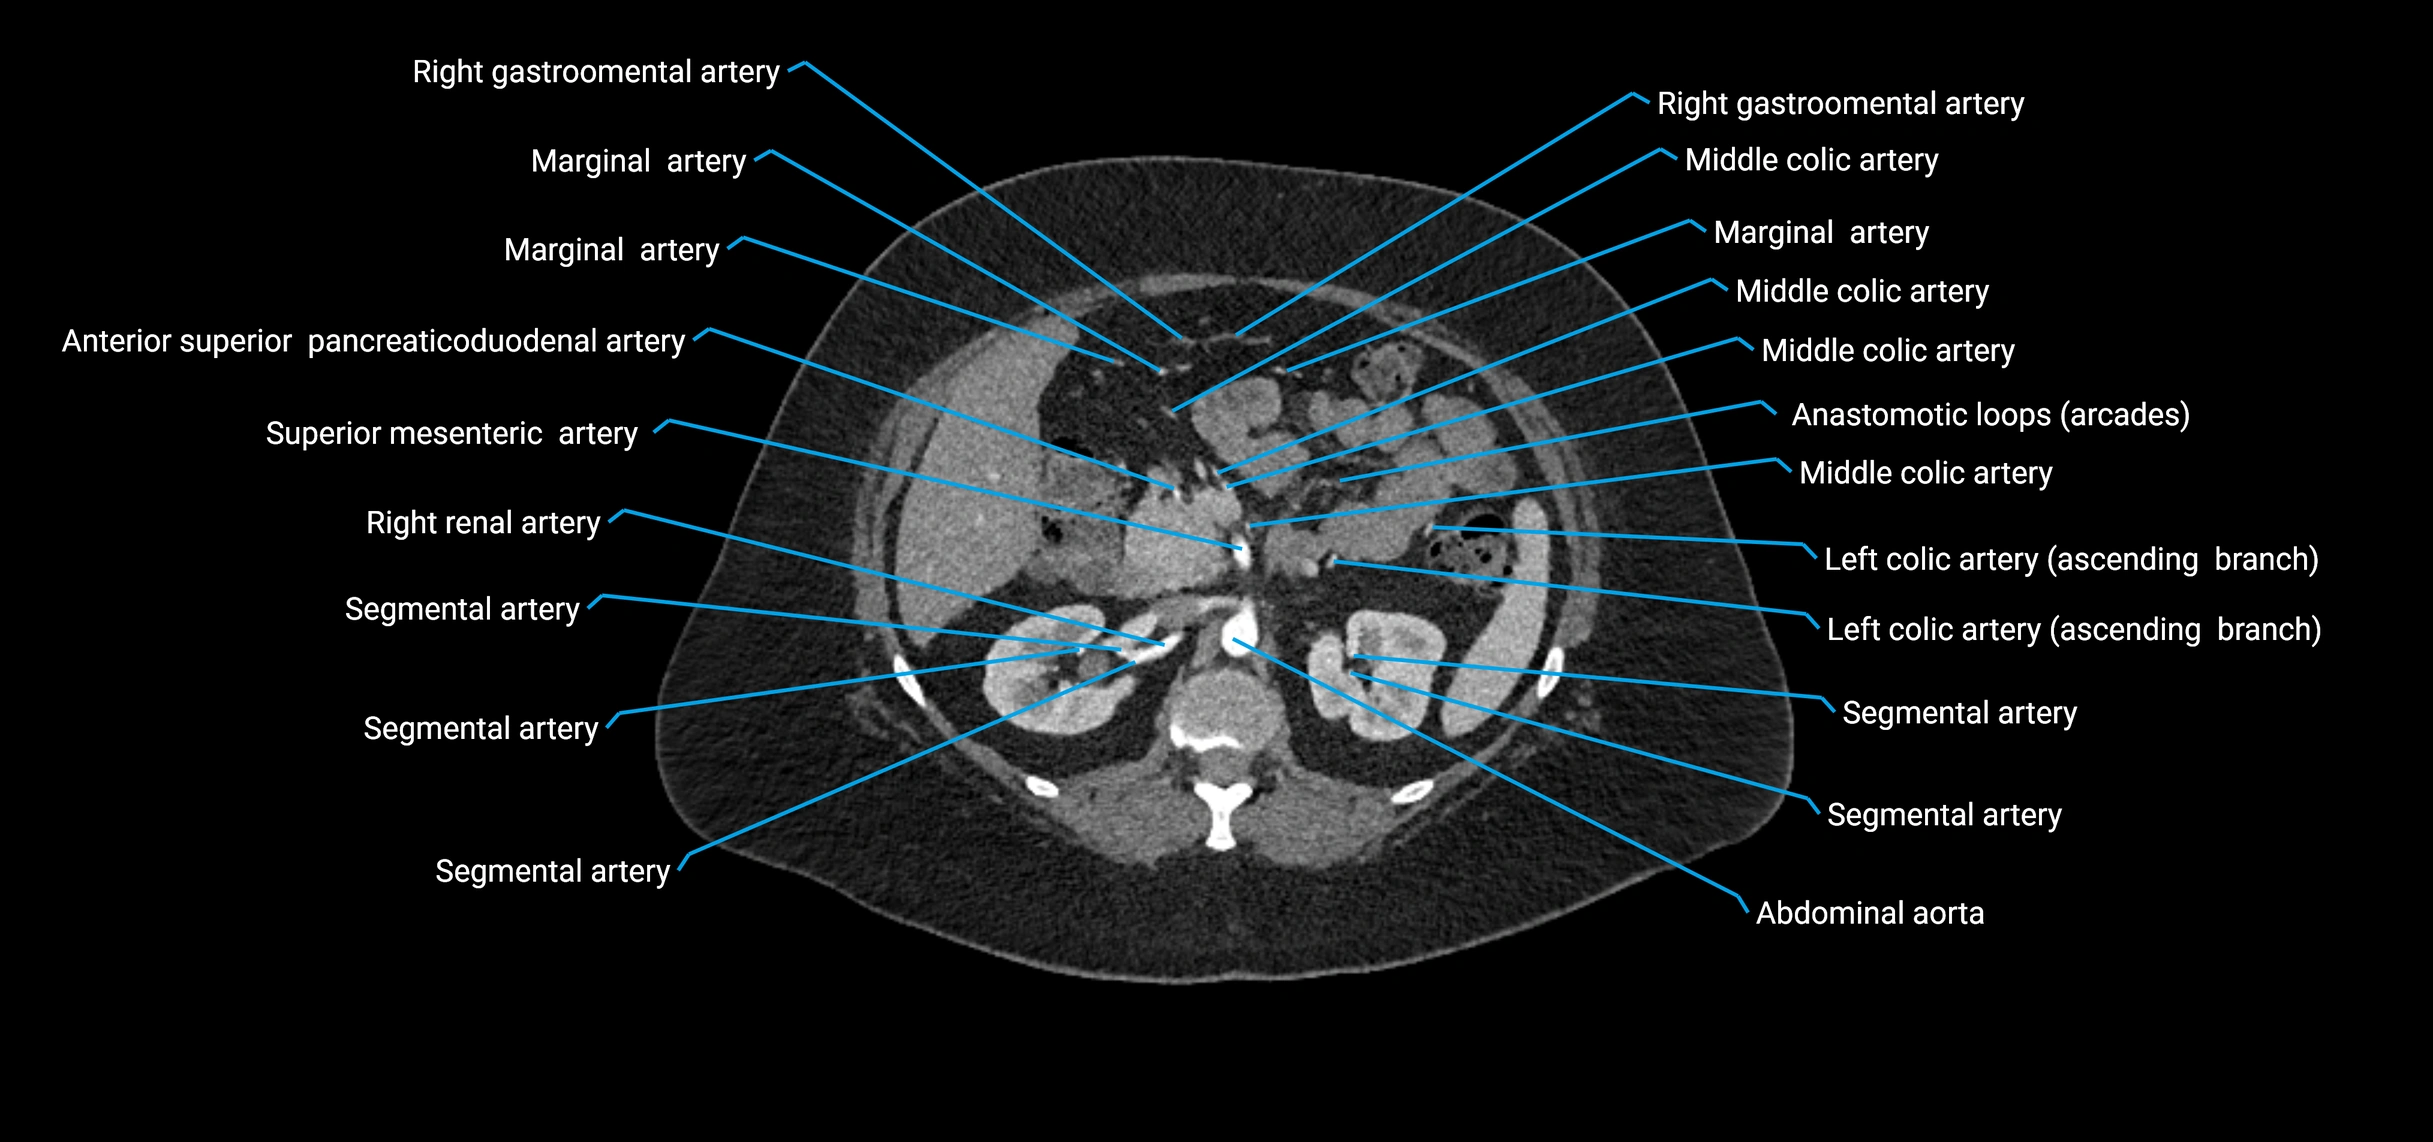

CT images

image

Contrast-enhanced CT (CTA):

• Gold standard for abdominal aortic imaging

• Provides excellent detail of lumen, wall, aneurysm, thrombus, and branch vessels

• Multiplanar and 3D reconstructions help in aneurysm measurement, stent graft planning, and dissection evaluation

• Unpaired visceral branches: celiac trunk, superior mesenteric artery (SMA), inferior mesenteric artery (IMA)

• Paired visceral branches: middle suprarenal arteries, renal arteries, gonadal arteries (testicular or ovarian)